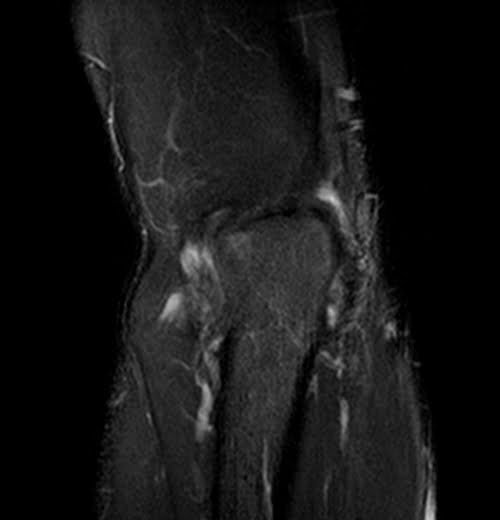

mri elbow coronal stir image 1 - MRI